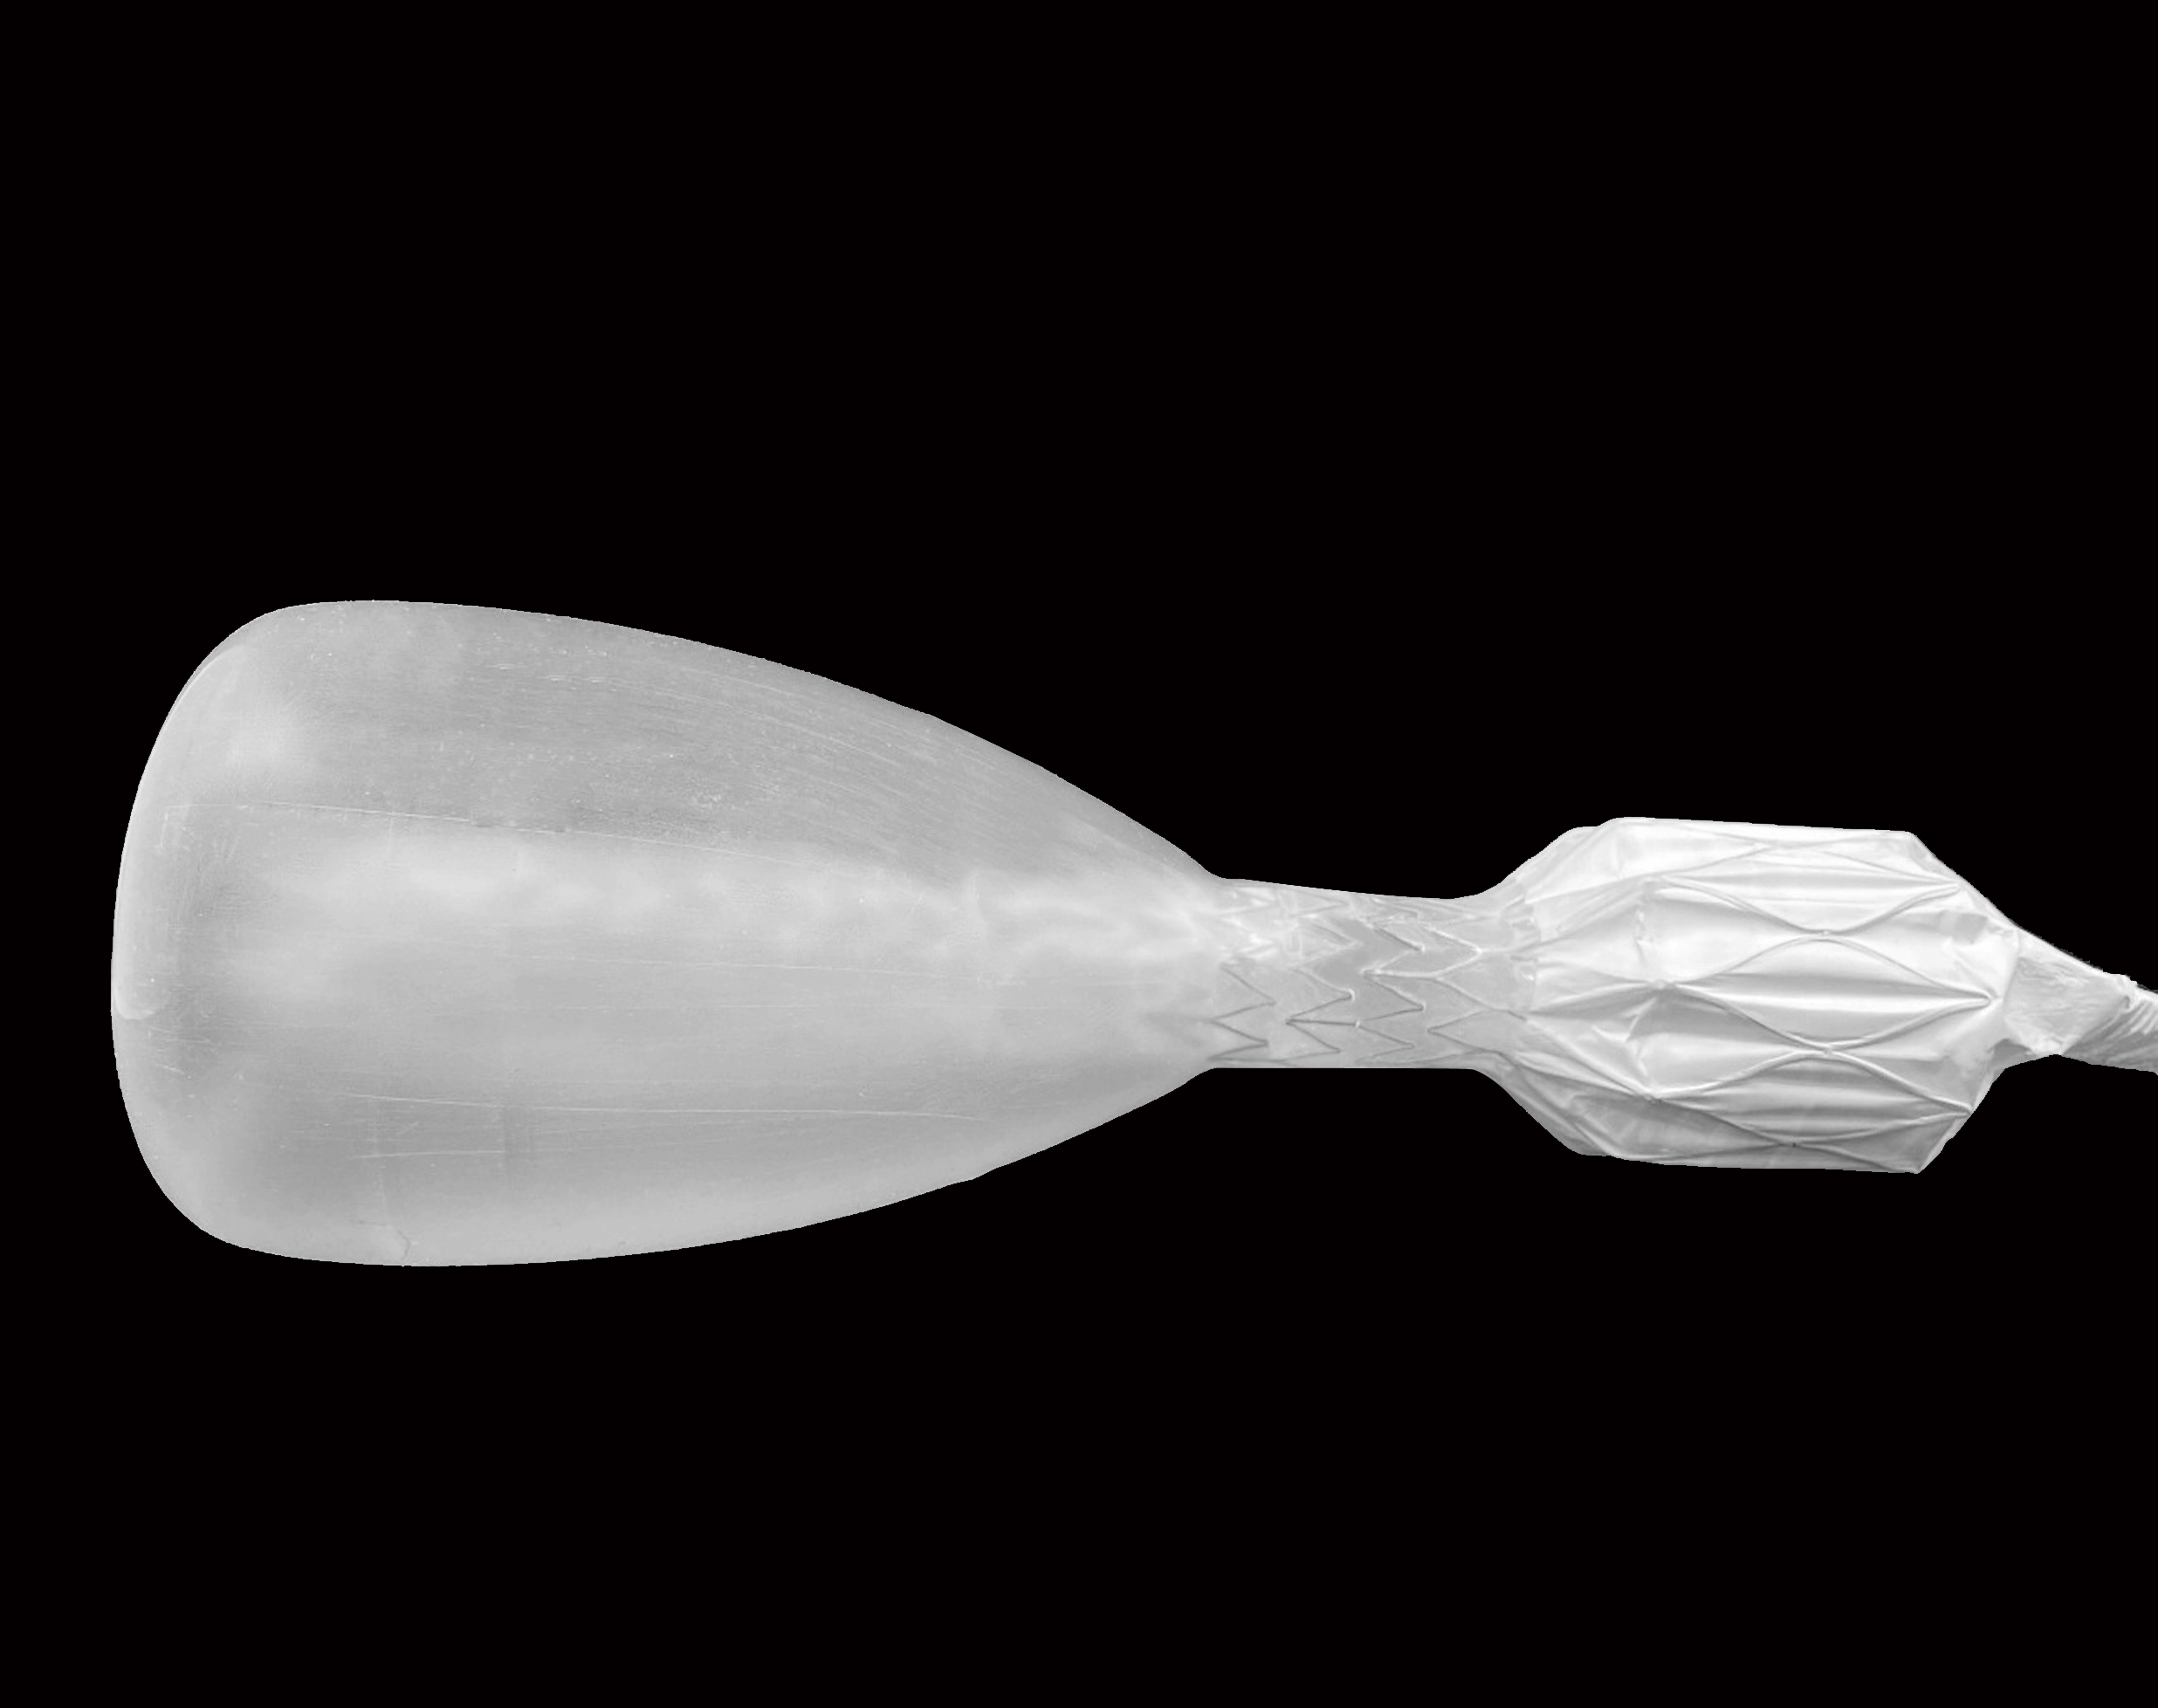

The first cut-free endoscopic treatment for diabesity, ForePass ® is able to replicate the most common types of metabolic surgery (Roux-en-Y Gastric Bypass, RYGB, BilioPancreatic Diversion, and Sleeve Gastrectomy). The first version of our product is aimed at RYGB.

Designed to replicate metabolic surgery without any cuts to internal organs. As effective on diabetes and obesity as metabolic surgery in animals.

ForePass ® replicates the three most common metabolic surgeries without requiring a single cut